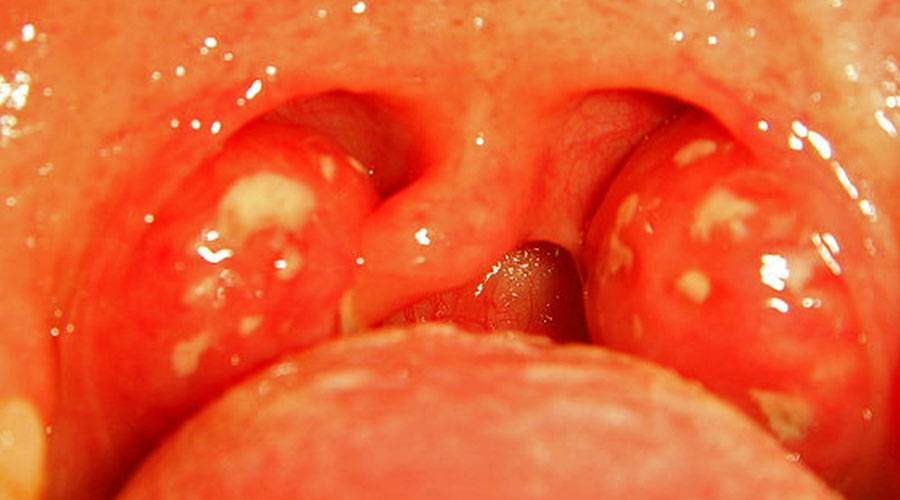

- небольшое увеличение миндалин, без наличия гнойных пробок;

- пузырьковые высыпания и образование язвочек в ротовой полости: на небе, миндалинах, глоточной части и на язычке;

Фолликулярная ангина — характеризуется сильной болью в горле, усиливающейся при глотании, и иногда отдающая в уши. Температура тела может повышаться до 38-40 °С, симптомы интоксикации — головная боль, слабость, озноб, тянущая боль в пояснице. Увеличиваются подчелюстные лимфатические узлы, на нёбе и миндалинах видны маленькие бело-желтые точки.

Лакунарная ангина у взрослых — протекает тяжелее, чем фолликулярная. Общие симптомы ангины такие же, только значительно выраженные. Нёбо приобретает ярко-красный цвет, на миндалинах отмечается налёт жёлтого цвета. В редких случаях температура поднимается до 40° С.